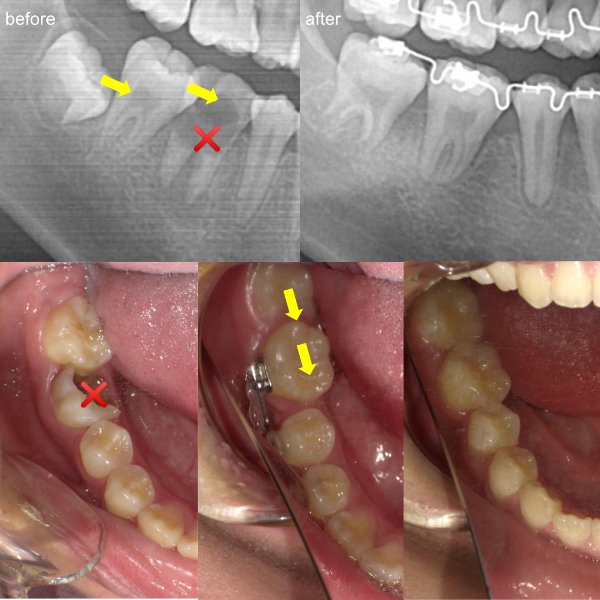

そういった様々な要因を取り除くことで、従来、小臼歯(4番、5番)を抜歯しなければ治療できない症例でも、非抜歯で治療可能となってきているのです。

機能的に小臼歯は非常に大切な歯であることから、最大限小臼歯を抜歯せずに治療できる治療方針を考えます。

また、下顎の位置関係、歯の傾きなどの原因を新素材ゴムメタルワイヤーで治療を行うことでほとんどの症例で小臼歯を抜歯しなくても治療可能になってきています。